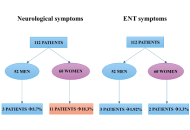

DOI: https://doi.org/10.37349/emed.2025.1001311 Long-term neurological and otolaryngological sequelae of COVID-19: a retrospective studyOpen AccessOriginal ArticleAim: COVID-19, a multisystemic syndrome caused by SARS-CoV-2, often results in long-term complications collectively referred to as long COVID. This study explores the persistence of neurological [...] Read more.Wael Abu Ruqa ... Antonio MinniPublished: April 21, 2025 Explor Med. 2025;6:1001310

Long-term neurological and otolaryngological sequelae of COVID-19: a retrospective studyOpen AccessOriginal ArticleAim: COVID-19, a multisystemic syndrome caused by SARS-CoV-2, often results in long-term complications collectively referred to as long COVID. This study explores the persistence of neurological [...] Read more.Wael Abu Ruqa ... Antonio MinniPublished: April 21, 2025 Explor Med. 2025;6:1001310